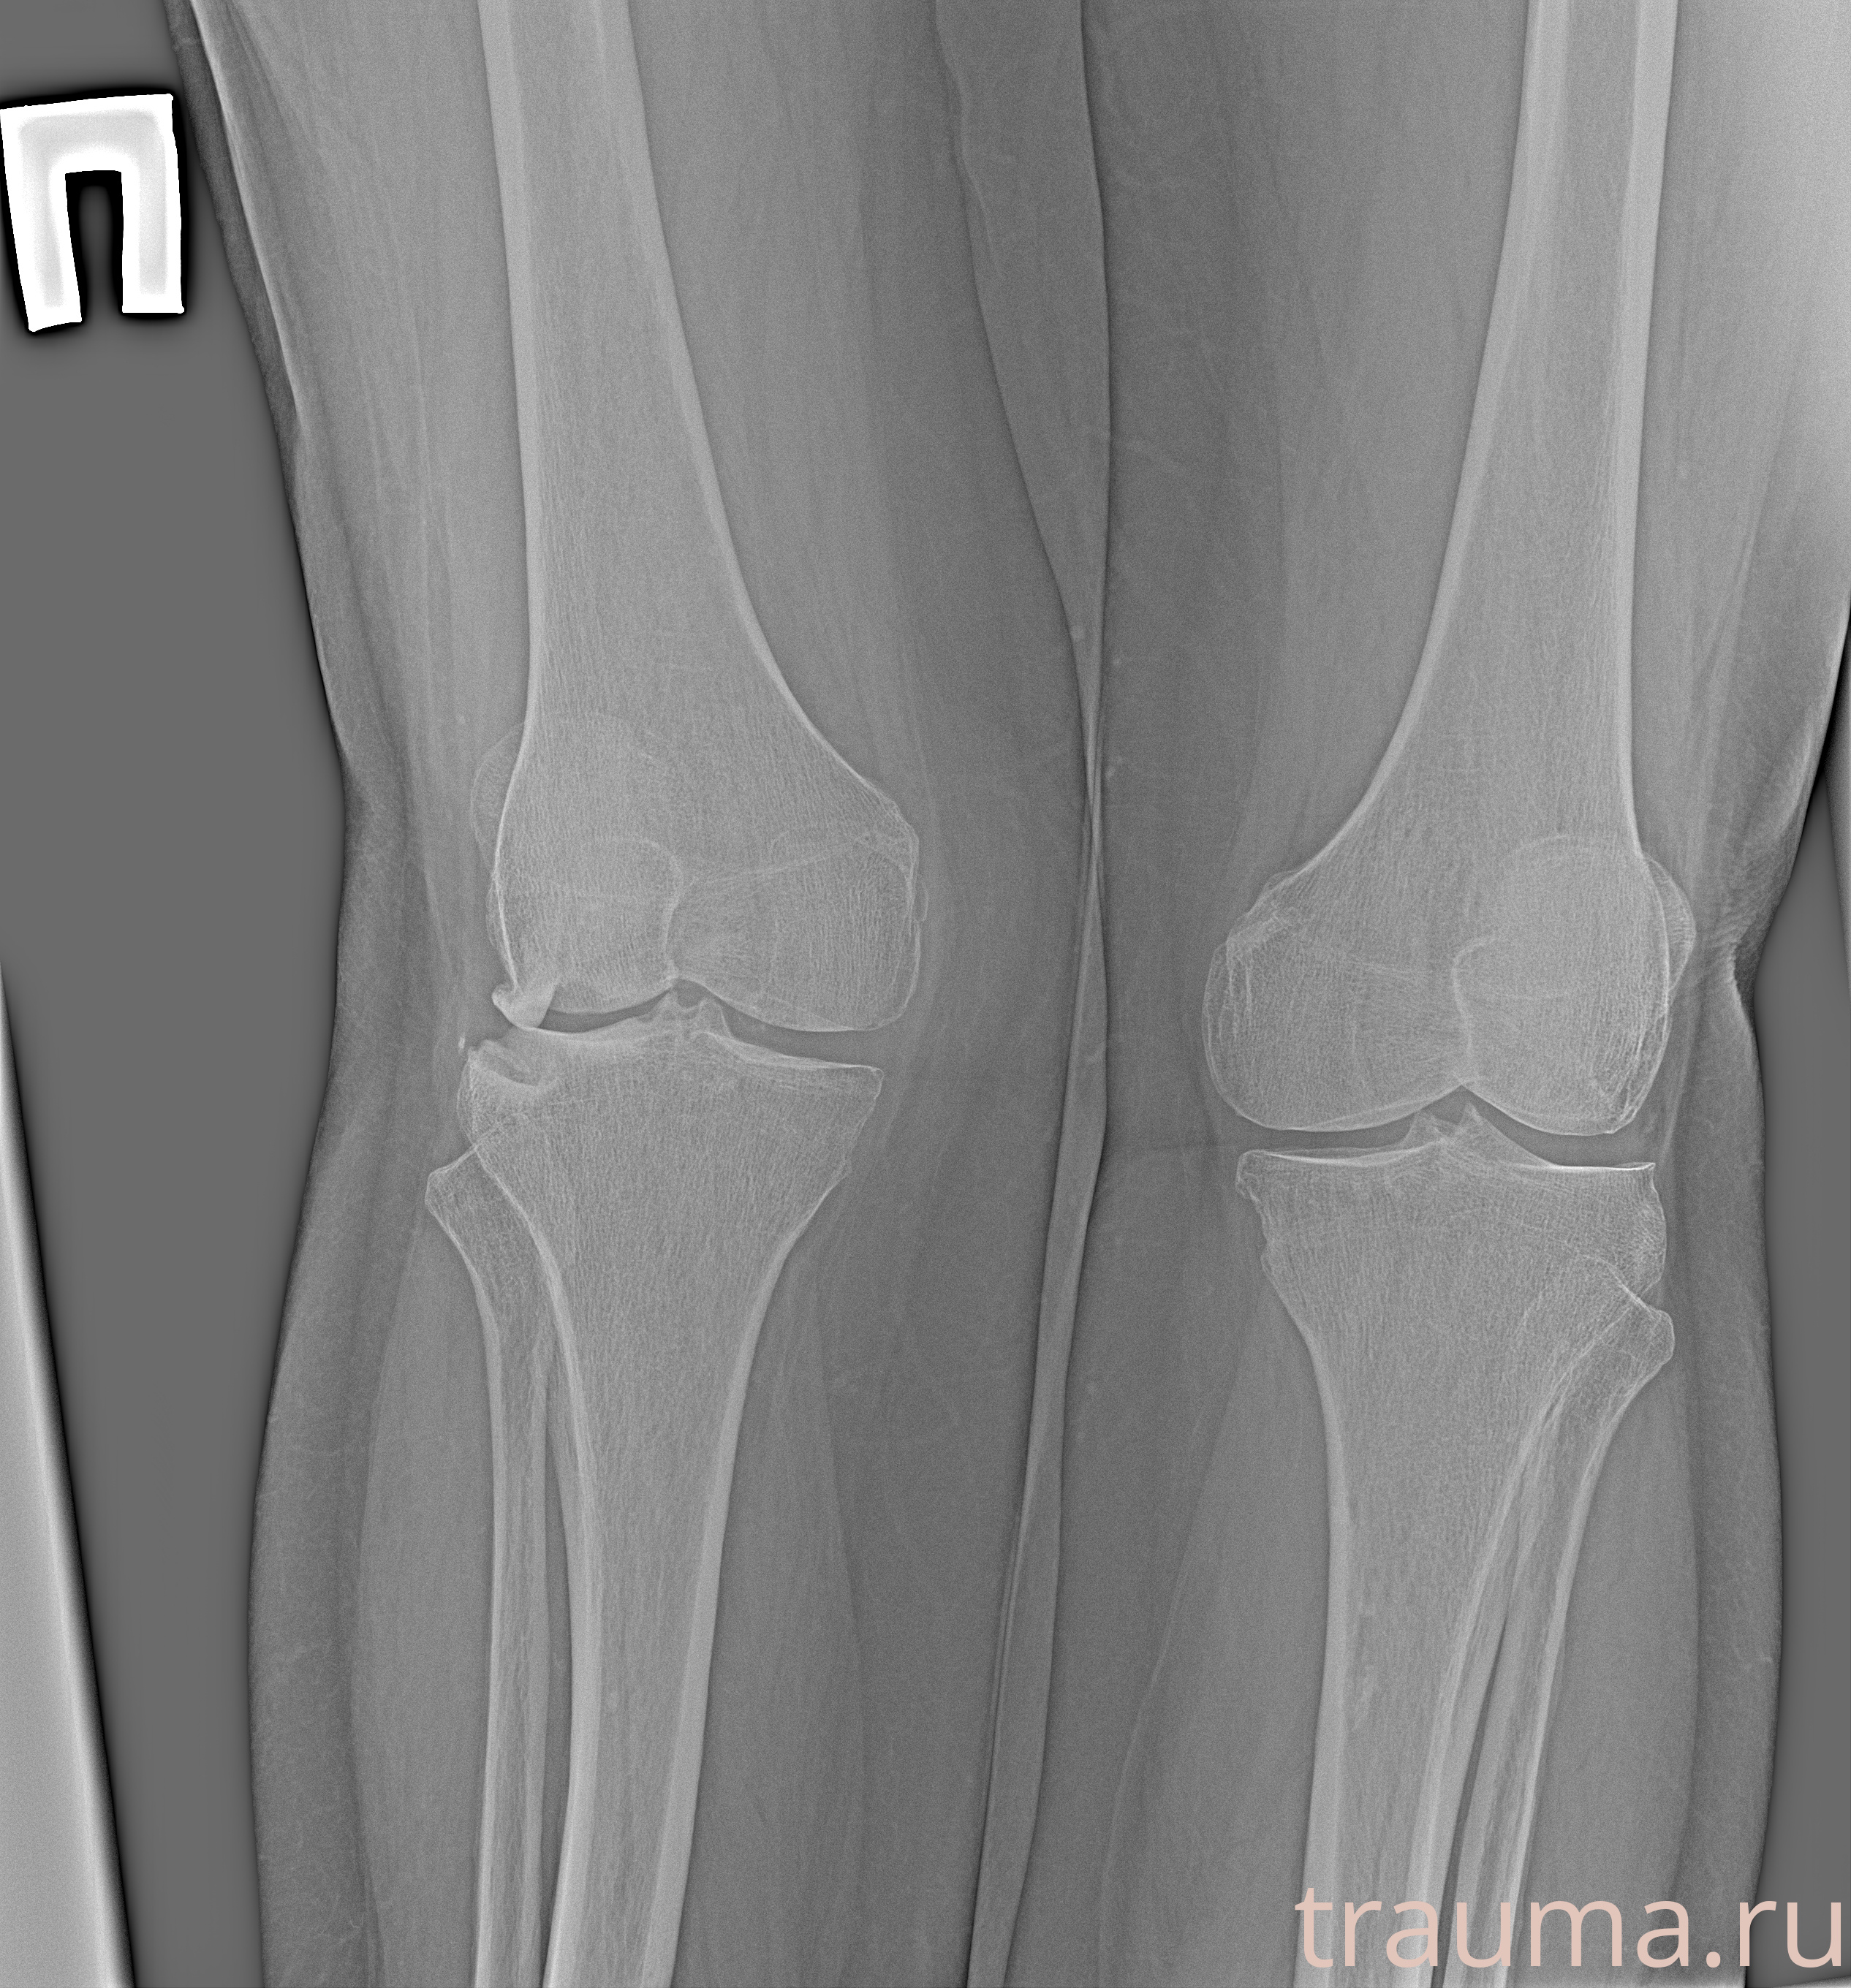

Рентгенограммы

Рентген на дому: по вашему адресу приезжает врач-рентгенолог, травматолог-ортопед с мобильным рентгеновским аппаратом, проводит диагностику травмы или заболевания, делает необходимые рентгенограммы, дает рекомендации по дальнейшему лечению. Получить качественные снимки в домашних условиях возможно благодаря уникальной методике, разработанной МосРентген Центром для института  Склифосовского